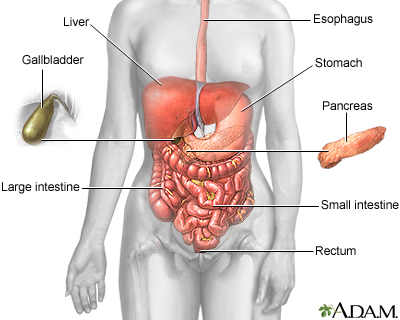

The gallbladder is an organ that sits below the liver. It stores bile, which is produced in the liver. Your body uses bile to digest fats in the small intestine.